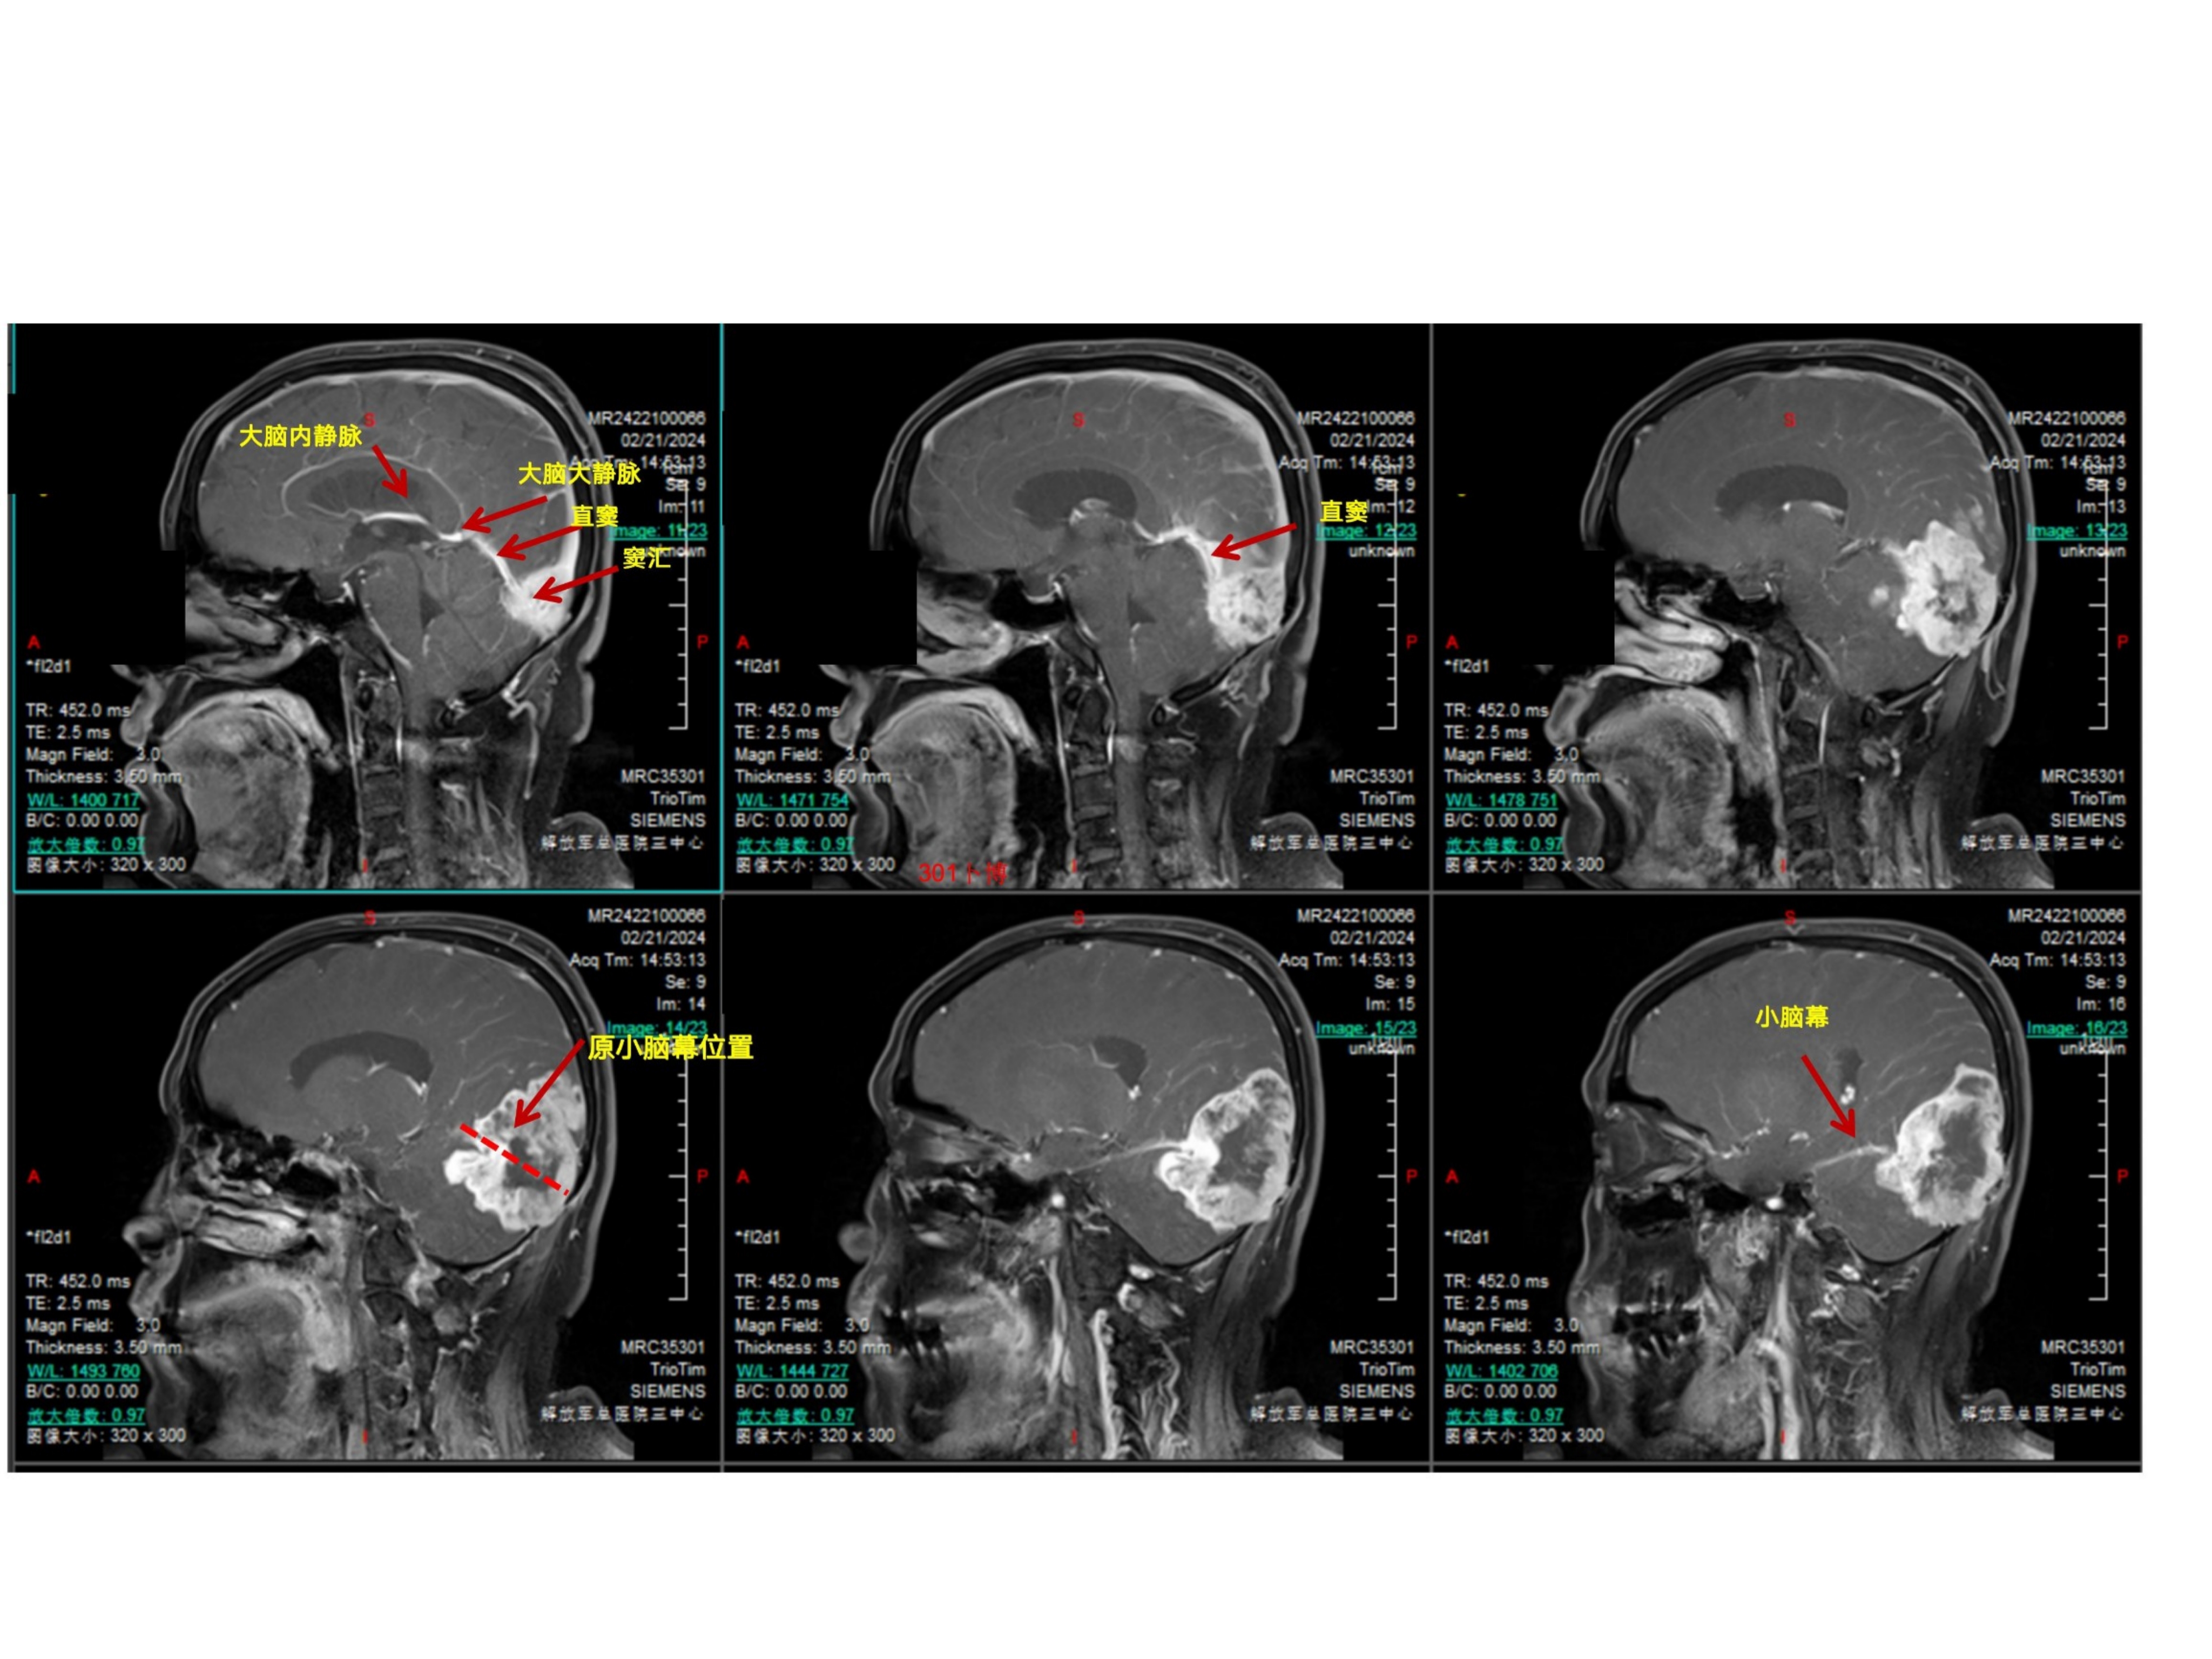

患者主要表现为双眼视力下降一个月余,加重3周。患者1个月前无明显诱因出现双眼视力下降伴视物重影,就诊当地医院行眼科相关检查,未能发现病因。3周前患者因头晕就诊徐州市中心医院,行头部CT提示颅内占位,进一步行头部磁共振检查提示脑膜瘤可能,建议手术治疗。1周前来我院就诊。查体:视力双眼0.6,右侧颞侧同向偏盲。眼底视乳头水肿。余神经系统查体阴性。诊断考虑为小脑幕-横窦-窦汇区脑膜瘤(侵袭性、WHO级,或者孤立纤维瘤)。手术前行栓塞两次,栓掉了大部分血供,同时看到左侧横窦闭塞,窦汇区通畅,静脉引流至对侧。手术采用俯卧位,导航下确认上矢状窦和窦汇区的位置。横窦已闭塞。中线旁跨横窦骨瓣。骨瓣已被肿瘤穿透。以上矢状窦后部为中心,星状剪开硬膜。抬起枕叶切除肿瘤以及受累及的横窦(已闭)小脑幕,向前(术野深面)切除至正常小脑幕边缘,幕间窦发达,一一电凝之。外侧结扎横窦乙状窦移行处,局部取枕部肌肉缝合加固,注意保护labbe静脉汇入点。向内导航下确认窦汇区的边缘。局部结构混乱,窦壁、大脑镰和小脑幕不通程度受累,正常窦壁侵犯无法准确辨认,只能导航确认一下边界。而且肿瘤充分切除减压以后局部膨隆,随呼吸节律波动,考虑窦壁菲薄。理想状态是切除受累及的窦壁并修补(见手绘文献图片)。考虑其为全脑静脉血管的最主要回流通道,没有准备好血管分流管,故未进一步切除受侵犯的窦壁。肿瘤次全切除。病理报告为孤立纤维瘤。术后三个月MRI增强提示切除理想,窦壁略增厚。建议补充伽马刀治疗。

DWI为等信号,有黑色现状结构,考虑为膨胀性生长的小脑幕结构。

增强后可见肿瘤穿透小脑幕,幕上下均有肿瘤

肿瘤并未穿过大脑镰到对侧,SSS后1/3通畅。

肿瘤并未穿过大脑镰到对侧,SSS后1/3通畅。周边脑组织水肿不明显明显。证明蛛网膜界面尚完整。